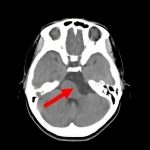

断層撮影

手術前2